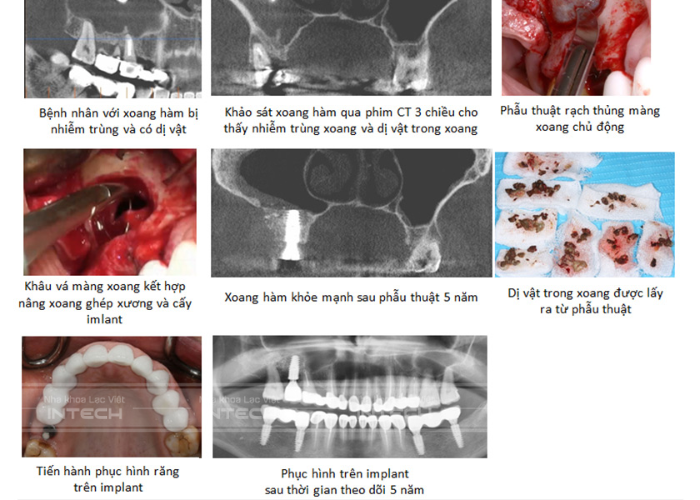

• Tình trạng xoang hàm đảm bảo điều kiện: Đáy xoang hàm thuận lợi, màng xoang không quá dày, không có dịch và trong xoang không có dị tật.